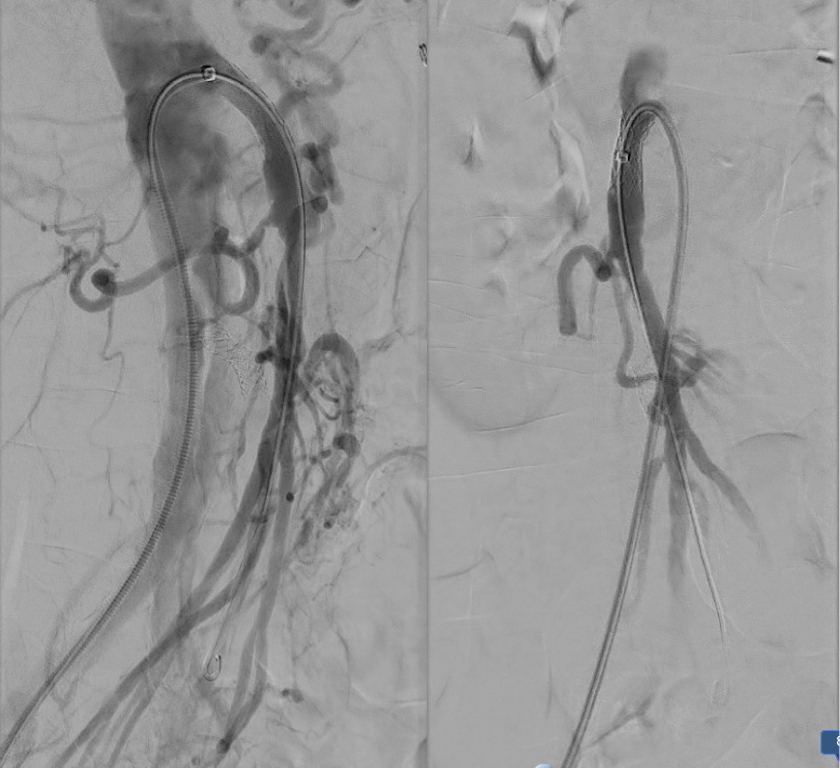

intervention fig 1.png

Advancing wire and sheath into iliac vein, crossing filter resulted in extravasation of contrast

Once position confirmed to be in the iliac vein, the vein was dilated to allow for greater ease of movement. In the case of the uncrossable filter, I switched to access from above via a right internal jugular vein access.

intervention fig 2.png

Dilating vein (left) for greater mobility, and crossing from above (R. IJV access)

Once the wire crossed into the iliac vein from above, it was captured and brought out. While ballooning by itself is inadequate for revascularization, it greatly eases wire capture and on the right, it was done simply by driving the wire from above into the sheath. Wire capture wins access across the iliocaval and IVC filter occlusion from below.

intervention fig 3.png

Wire passage across IVC filter into right and left systems